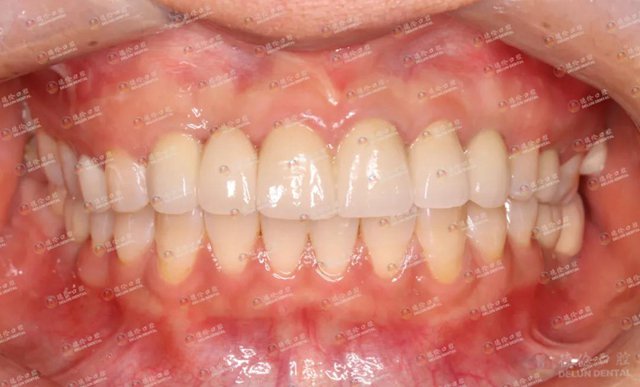

刘女士重获一口好牙